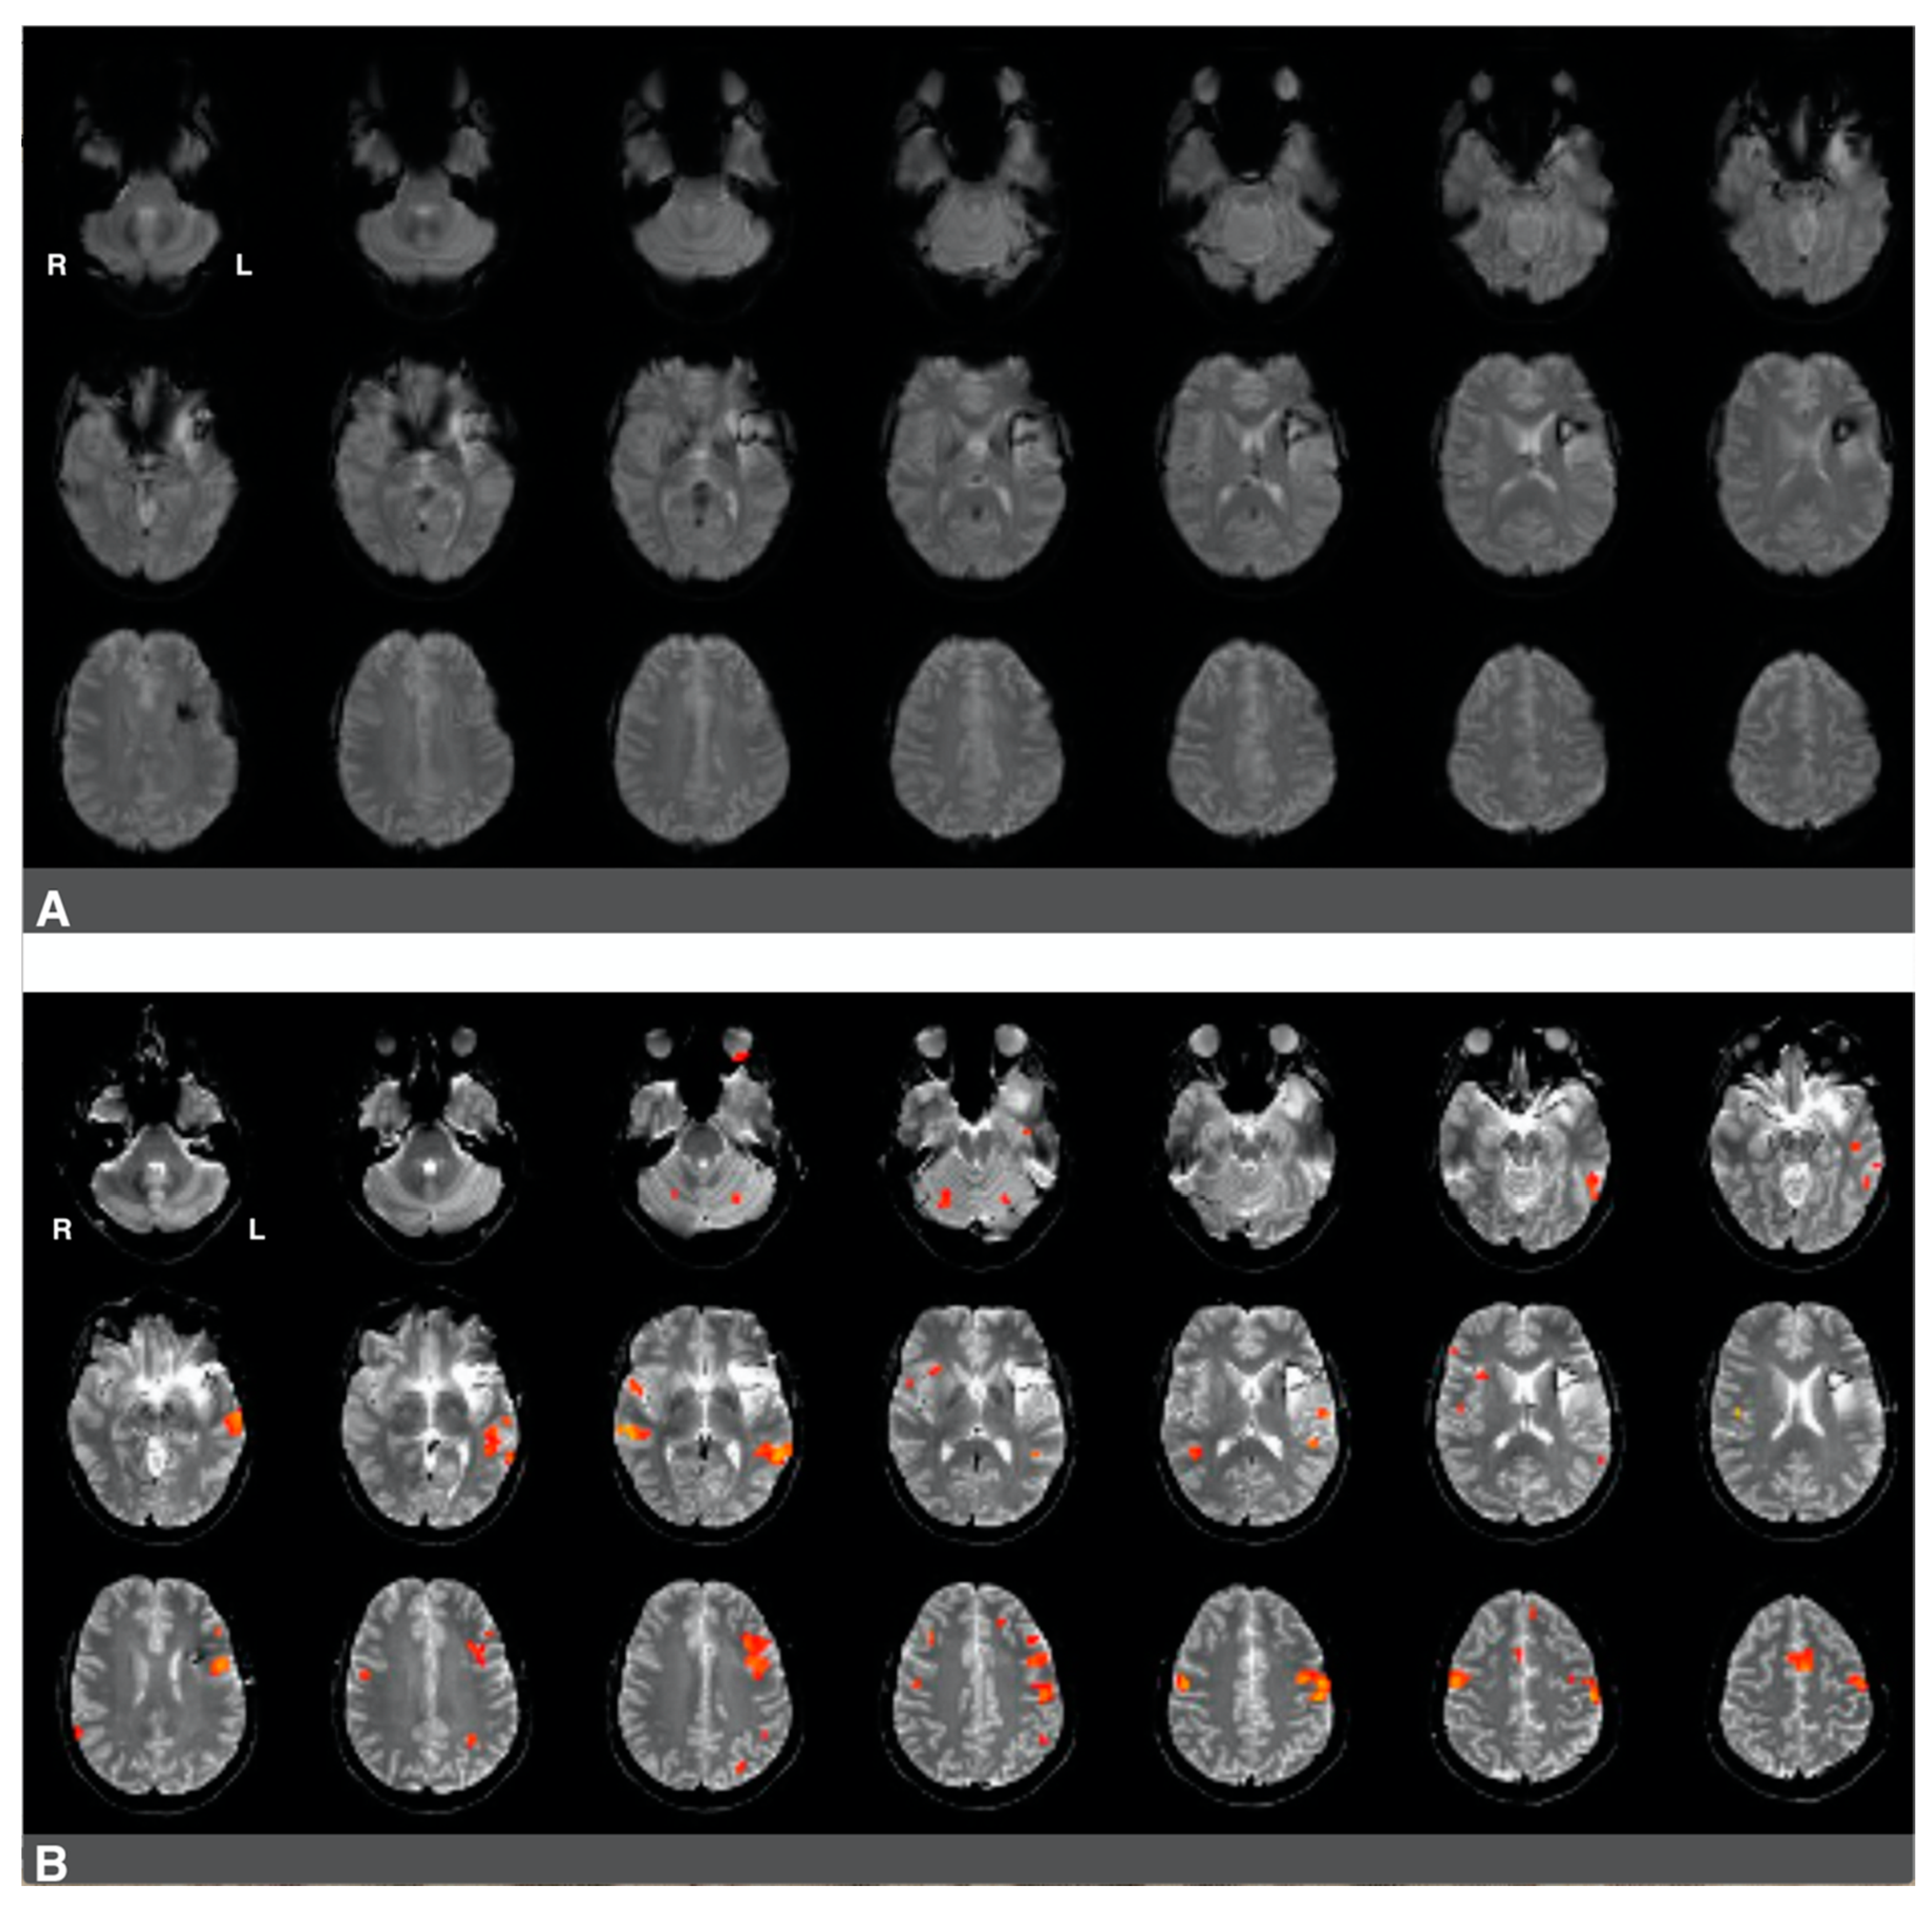

Figure 5.

Predominantly left hemisphere activations in a patient with a low-grade glioma in the left hemisphere. Panel (A): a raw functional image with a notable absence of activation in the left frontal region corresponding to Broca’s area. The absence of activation may be related to artifact and edema from prior resection in the area. Panel (B): Language activation consistent with Broca’s area during pre-surgical fMRI. Activations in the right hemisphere were much less significant in this patient.

The second case was a 37-year-old, left-handed female diagnosed with stage II astrocytoma. The patient suffered from mild aphasia. The patient underwent chemo- and radiotherapy and had a history of seizures. Language laterality based on the whole-brain approach was 0.46, and it was 0.65 using Broca’s ROI and 0.54 using Wernicke’s ROI. Activation consistent with Broca’s area was observed in Figure 5B, images one to four of the third row, immediately adjacent to the superior aspect of the lesion and prior resection site. Activations in the right hemisphere were much less significant in this patient. There was an artifact from the prior surgery in the area of the lesion, which is likely obscuring further activation in Broca’s area in the left hemisphere (Figure 5A).